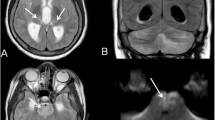

A 4-year-old Caucasian girl presented with a 20-min generalised, tonic–clonic seizure following 2 days of fever and coryza. She was pyrexial (38.9°C) and had a herpetic lesion (HSV type 1 DNA-positive) on her upper lip. Seizures continued warranting sedation and ventilation. She was commenced on IV ceftriaxone, IV acyclovir and oral oseltamivir. 2009 H1N1 virus RNA was detected in upper and lower respiratory samples. CSF analyses were negative for H1N1 and HSV PCR. EEG on day 2 showed continuous generalised slow wave activity with no epileptiform discharges. She remained encephalopathic and developed upper motor neuron signs. Brain MRI on day 2 was suggestive of ANE. Due to the clinical and neuroimaging severity, she was given intravenous immunoglobulin (IVIG), and oral oseltamivir therapy was empirically converted to IV zanamivir. Her clinical recovery was excellent with neurological normalisation over 7 days. At 3 and 9 months, she remained neurologically normal and had fully integrated back in school (outcome 1).

Of the 69 reported cases, brain neuroimaging data was available in 42. Neuroimaging was normal in 42% (18/42) of patients. Cortical and sub-cortical white matter signal changes (16%; 7/42) and neuroimaging features of ANE (17%; 7/42) are the commonest neuroimaging changes described. The importance of acute and follow-up neuroimaging is underlined by our series. Acutely, only two of our five cases had abnormal neuroimaging: one showed evidence of ANE and another showed non-specific white matter changes. Although initial neuroimaging was normal for the other three patients, the interval MRI was abnormal in two. One showed increased signal in periventricular distribution bilaterally, the other revealed significant loss of cerebral volume. Normal acute imaging followed by brain atrophy is well described with IAE, most patients being left with marked neurological sequelae [2, 46], as in our patient. Patients infected with the 2009 H1N1 strain with ANE, basal ganglia involvement and volume loss on neuroimaging had poorer outcome (Table 1).